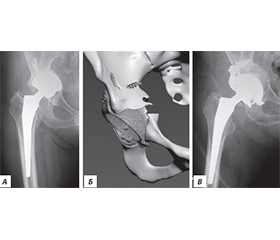

Резюме

Актуальність. Ендопротезування кульшового суглоба сьогодні є одним із найбільш поширених і водночас ефективних методів лікування. Проте у віддалені терміни після операції виникає проблема розвитку нестабільності елементів протеза, що потребує повторних оперативних втручань, які належать до категорії складних і технічно трудомістких. Мета дослідження: на основі власного досвіду ревізійного ендопротезування кульшового суглоба та даних літератури обговорити питання планування і вибору тактики оперативного лікування для покращення результатів. Матеріали та методи. Було проаналізовано результати 146 ревізійних ендопротезувань кульшового суглоба у пацієнтів з асептичною нестабільністю елементів протеза за 11 років (2012–2022). Серед обстежених було 93 жінки та 53 чоловіки, вік пацієнтів коливався від 24 до 82 років (середній вік становив 64,5 року). Функціональне відновлення хворих оцінювали за шкалою Harris Hip Score. Результати. Нестабільність ацетабулярного компонента й ніжки протеза спостерігали у 34 пацієнтів, лише ацетабулярного компонента — у 48 осіб, лише ніжки — у 32 хворих, вивих протеза — у 9, стирання поліетиленового вкладиша — у 5, перелом керамічної головки — у 2, перелом ніжки протеза — в 1, перипротезні переломи — у 15 пацієнтів. Середній показник шкали Harris Hip Score становив 79,3 бала (95% довірчий інтервал: 73,9–84,7). Відмінні або добрі результати досягнуто у 52,8 % пацієнтів, задовільні — у 29,5 %, незадовільні — у 17,8 %. Загальна частота післяопераційних ускладнень становила 7,53 %. Висновки. У ревізійному ендопротезуванні доцільно віддавати перевагу безцементним системам фіксації з обов’язковим застосуванням кісткової пластики при дефіциті кісткової тканини. Найбільш ефективними виявилися ацетабулярні чашки з покриттям екструдованим титаном, а також ревізійні й індивідуально виготовлені конструкції. При ревізії стегнового компонента ніжка Wagner продемонструвала стабільні клінічні результати та надійність фіксації.

Background. Hip arthroplasty is one of the most common and effective surgical methods of treatment. However, over time, the problem of prosthetic component instability arises, requiring revision procedures. The aim was to analyze own experience of revision hip arthroplasty and literature data, with a focus on planning and surgical strategy to improve outcomes. Materials and methods. We analyzed the results of 146 revision hip arthroplasties performed in patients with aseptic prosthetic component instability in 2012–2022. The study cohort included 93 women and 53 men, aged 24–82 years (mean age 64.5). The functional recovery of patients was assessed using the Harris Hip Score scale. Results. Instability of both the acetabular component and femoral stem was observed in 34 patients; isolated acetabular component instability in 48; isolated femoral stem instability in 32; prosthetic dislocation in 9; polyethylene liner wear in 5; ceramic head fracture in 2; femoral stem fracture in 1; and periprosthetic fractures in 15 patients. The mean Harris Hip Score was 79.31 units (95% CI: 73.9–84.7). More than half of the patients (52.8 %) achieved excellent or good results, 29.5 % — satisfactory, and 17.8 % — unsatisfactory. The overall rate of postoperative complications was 7.53 %. Conclusion. In revision hip arthroplasty, preference should be given to cementless fixation systems with mandatory bone grafting in cases of bone deficiency. The most effective implants were acetabular cups with extruded titanium coating, as well as revision and custom-made components. In femoral component revisions, the Wagner stem demonstrated stable clinical outcomes and reliable fixation.